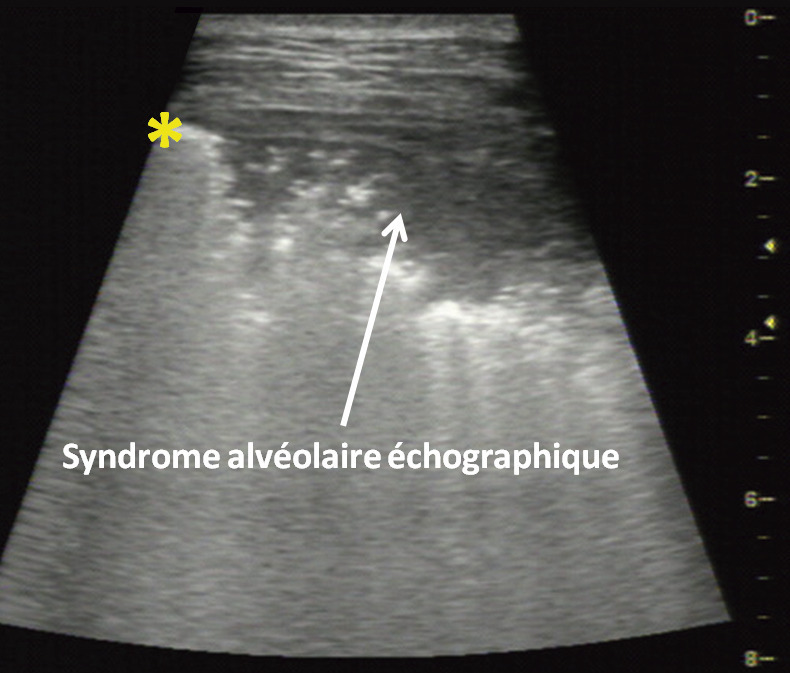

C’est le cas des pneumonies : l’air des alvéoles est remplacé par des sécrétions, du pus, des cellules inflammatoires, et cette condensation est facilement visible à l’échographie (fig. 3 ). Différentes études montrent que la quasi-totalité des pneumonies touchent la périphérie du poumon et ont une traduction échographique. L’échographie aux urgences a une sensibilité équivalente ou supérieure à la radiographie thoracique dans les diagnostics de pneumonies.4

C’est le cas des pneumonies : l’air des alvéoles est remplacé par des sécrétions, du pus, des cellules inflammatoires, et cette condensation est facilement visible à l’échographie (